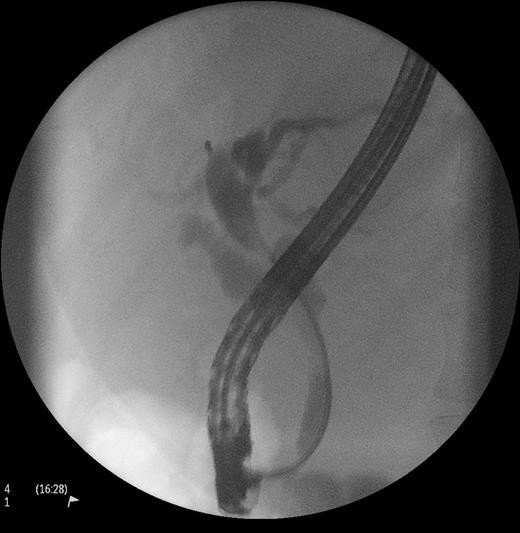

The liver function tests revealed an obstructive picture. Bilirubin level was 86 µmol/l (normal 2–24 µmol/l). Gamma glutamyl transferase (GGT) and alkaline phosphatase were 347 and 340 U/l, respectively. In view of prior history of choledocolithiasis, an ERCP was undertaken. An eccentric stricture at the level of the junction of cystic duct and CBD was seen along with a dilatation of proximal the bile duct. There were no ductal calculi. A plastic stent was inserted to relieve the jaundice (Fig. 1). These findings raised the suspicion of a malignant process, and a computerized tomography (CT) scan of the chest, abdomen and pelvis was consequently performed.